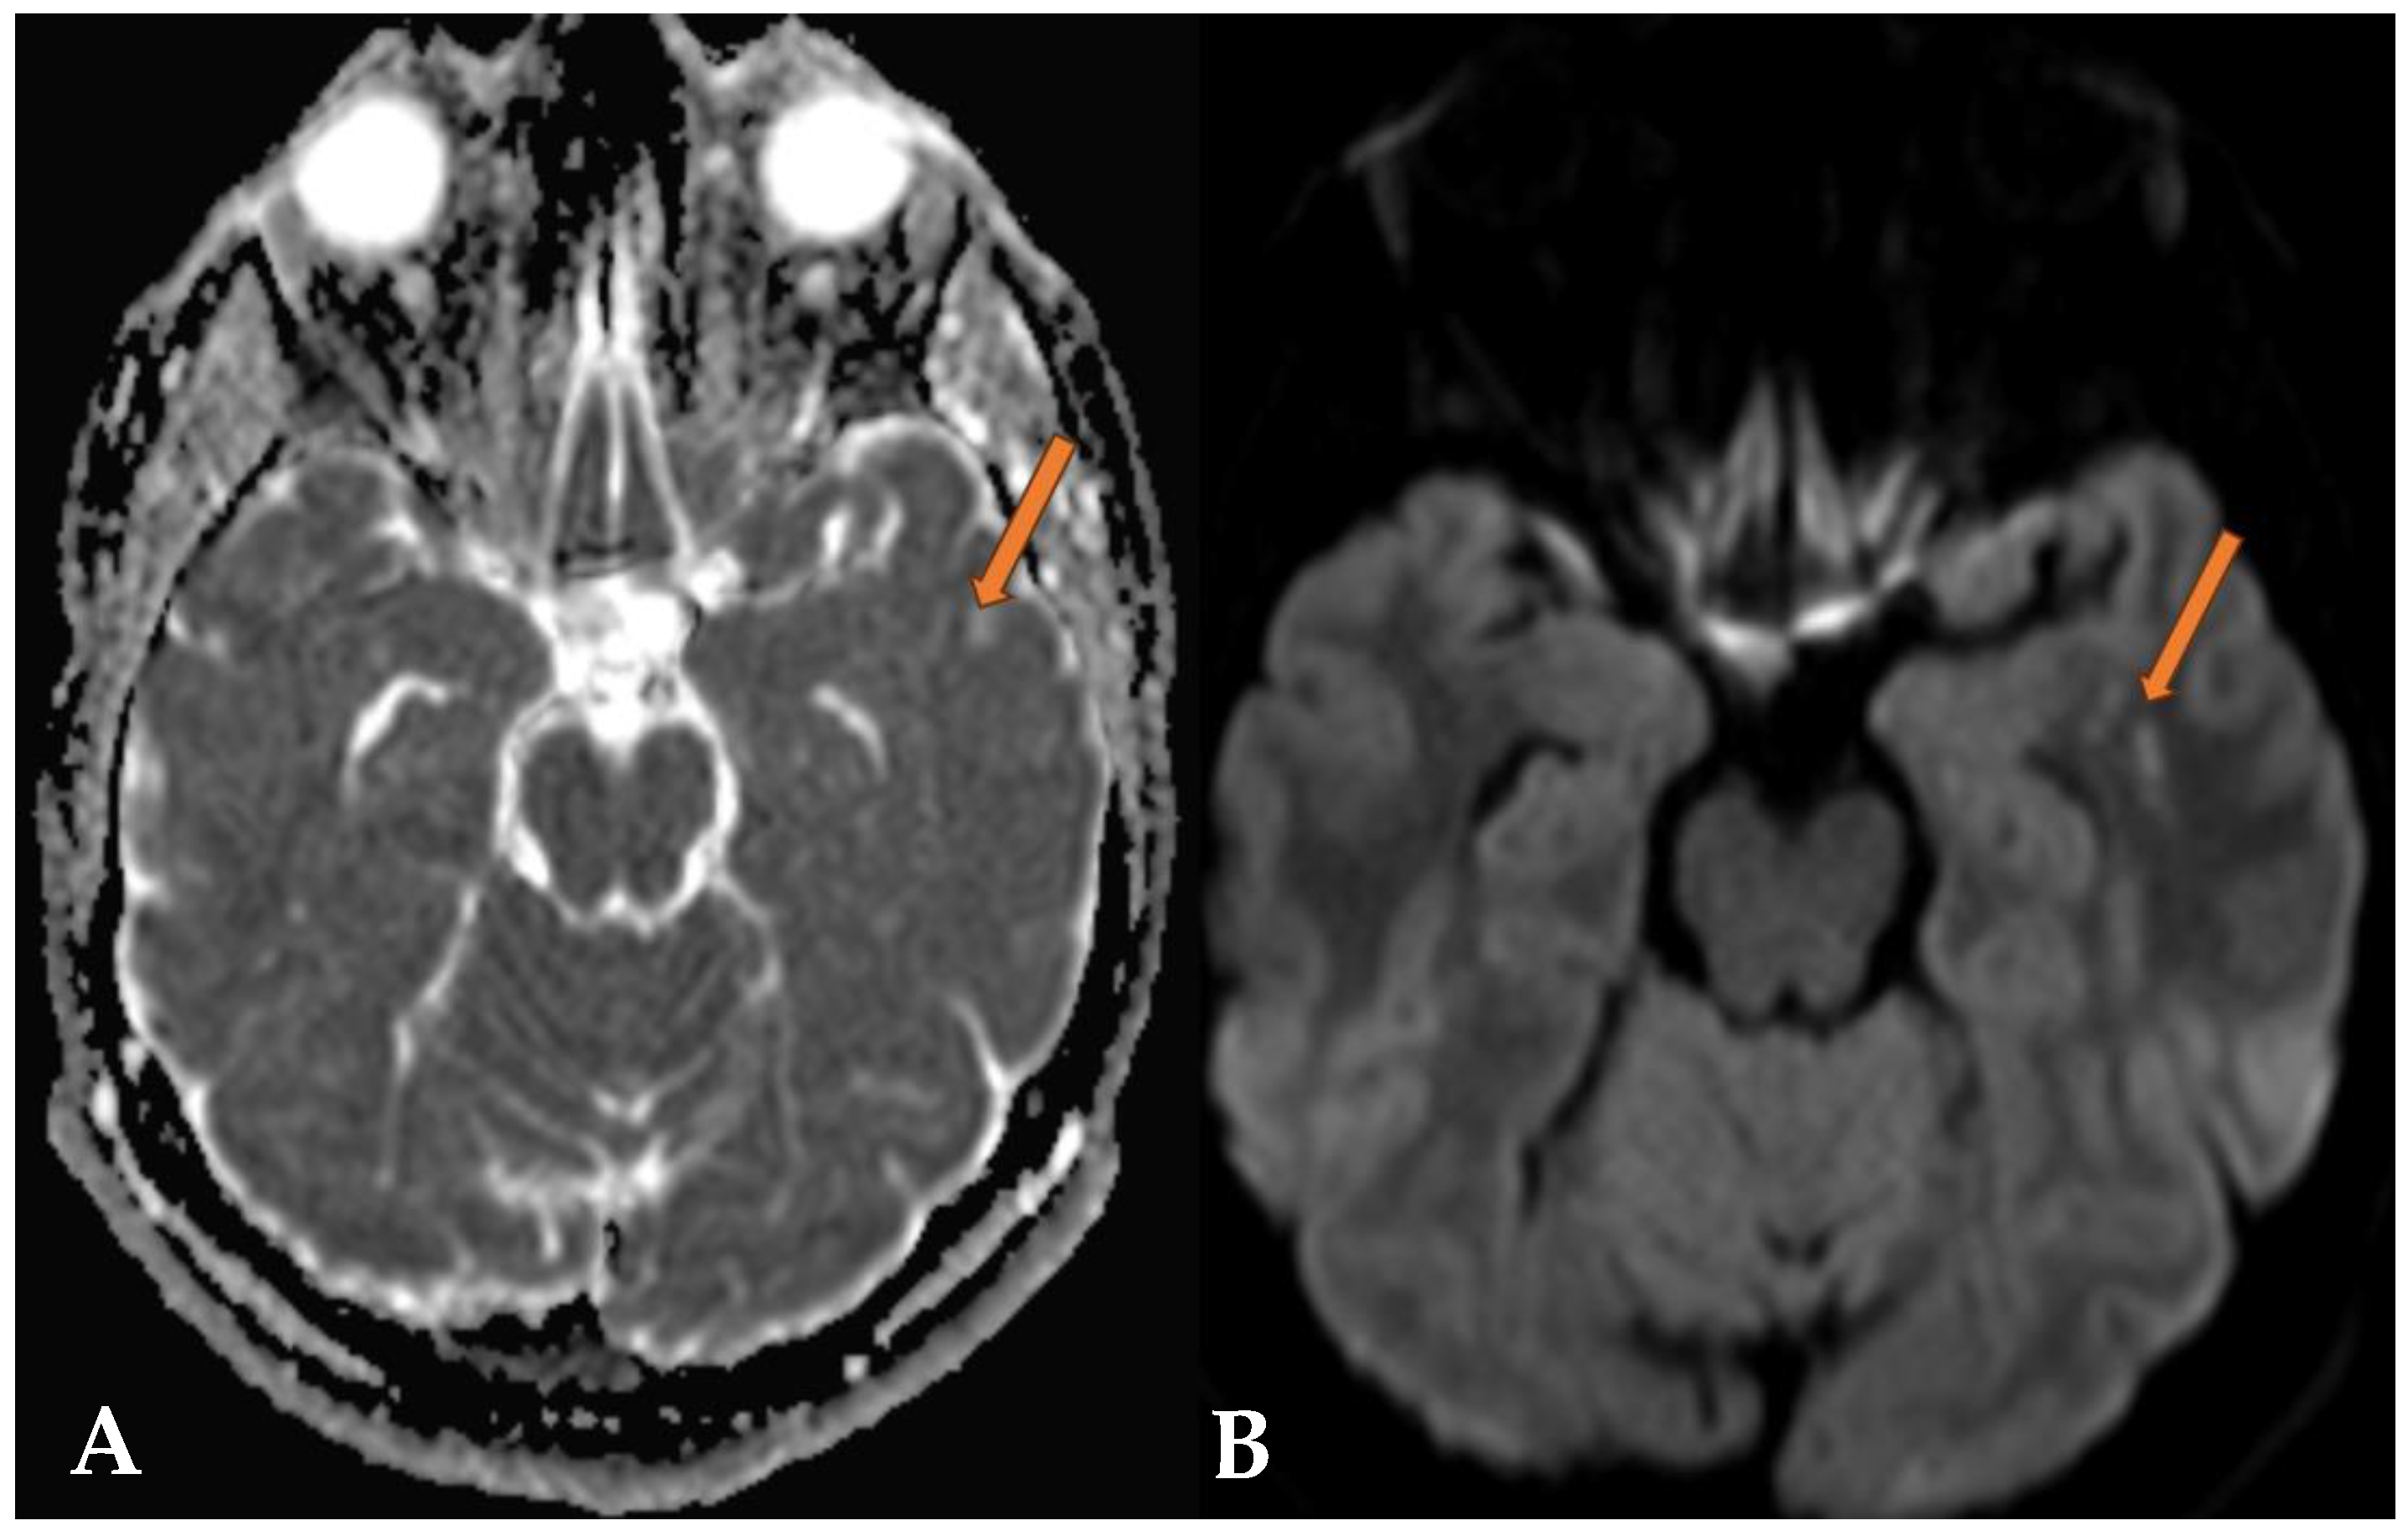

2.1. Case 1